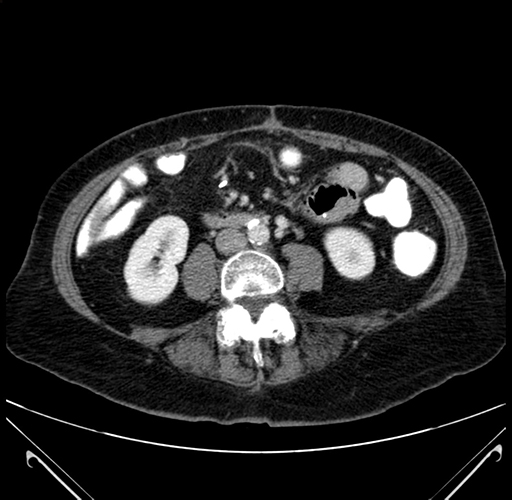

Pre-Chemo: Axial Venous

Axial Venous